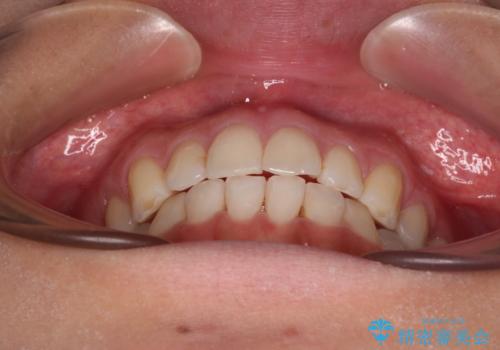

前歯の重なりをインビザライン・モデレートで矯正治療

- 上下前歯の重なりを気にして来院された患者様です。

安価なインビザラインパッケージを用いての治療を希望されており、デコボコの程度が中等度であったため、インビザライン・モデレートを用いて矯正治療を行うこととしました。

インビザライン・モデレートは、製作できるアライナーの枚数に制限があるため、移動可能な量に限りがあるものの、インビザライン・ライトよりも枚数が多いため、幅広い症例に対応可能です。